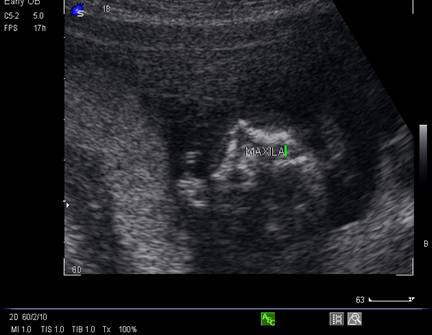

Fig. nr. 167. Fata fetala la ecografia 3D/4D

Fig. nr. 168. Plan de sectiune oblic coronal, derivat din planul XIV, ce pune in evidenta maxilarul osificat la 16 sapt.